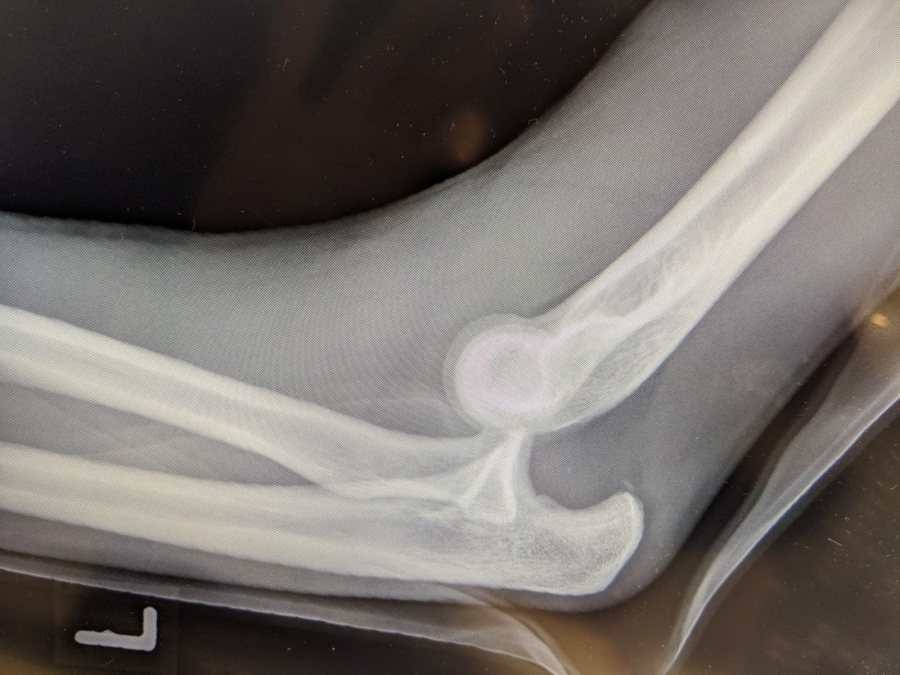

Wendrichs Röntgenbild.

Wendrichs Röntgenbild. Wendrichs Röntgenbild.

Es war der 30. Dezember des vergangenen Jahres als der Sportler des LAZ Soest wie so oft auf der Hochsprungmatte in der Dortmunder Helmut-Körnig-Halle seine Turneinheit absolvierte. „Ich habe mich in der Luft etwas zu schnell gedreht, bin dann in Rücklage gelandet, von der Matte gefallen und habe mich schließlich auf dem Arm abgestützt“, erinnert sich der 24-Jährige heute. „Als der Schmerz nicht aufhörte wusste ich: Das ist etwas Schlimmeres.“ Wenig später im Krankenhaus kam dann die Diagnose: „Luxation im linken Ellenbogengelenk“. Sprich: Das Gelenk ist nicht mehr dort, wo es hingehört, es ist ausgerenkt. „Das ist eine richtig schwere Verletzung“, erfuhr Wendrich spätestens nach dem Blick auf die Röntgenbilder. Auch das Radiusköpfchen, ein Knochen am oberen Ende der Speiche, brach bei dem Sturz. Als Wendrich das Krankenhaus verließ, waren Ober- und Unterarm im 90-Grad-Winkel eingegipst und es war klar: Die Hallensaison ist gelaufen.